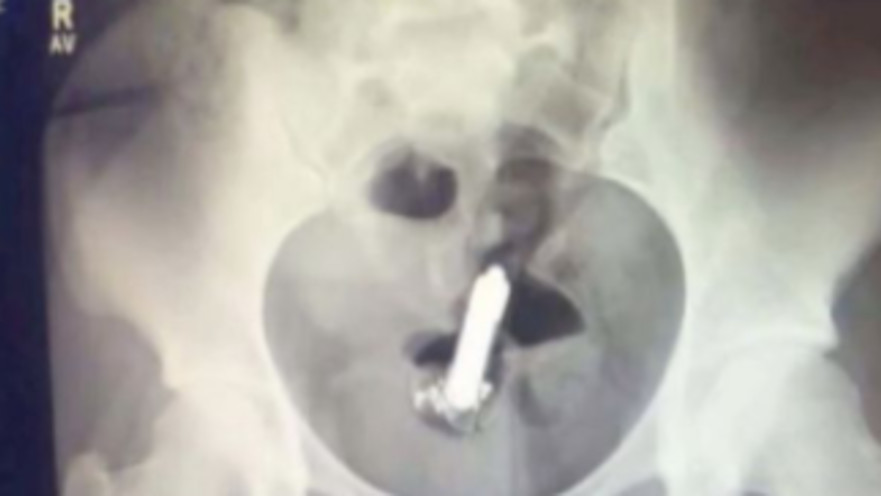

אישה הפכה לוויראלית ב-TikTok, כשחשפה את צילום הרנטגן שעברה לאחר שהשתמשה בוויברטור, והוא נותר תקוע "עמוק בפנים". היא שיתפה את הסיפור במלואו עם העוקבים שלה, על שנזקקה לניתוח כדי לחלץ את ה"פריט"

הוויברטור נתקע עמוק מדי, נזקקה לטיפול רפואי כדי לחלץ אותו | צילום: צילום מסך טיקטוק

היא הוסיפה: "העדפתי להמתין לבוקר. ניסיתי לישון וזה היה די קשה, כי הרגשתי אותו מזמזם לי בעמוד השדרה. בסופו של דבר נרדמתי, וכשהתעוררתי - הוא היה כבוי. סביר להניח שהסוללה נגמרה. הלכתי למיון ואמרו לי שאני צריכה לעשות צילום, לא לפני שהם ניסו להוציא את הכלי משם באופן ידני - פעמיים. לאחר שלא הצליחו, הכניסו אותי לחדר ניתוח וכשהתעוררתי, בחדר ההתאוששות, הוא פשוט היה מונח על השולחן ליד המיטה שלי. הרמתי אותו כדי להבין שוב איך הכל קרה, וכשלחצתי על כפתור ההפעלה, הוא עבד!".